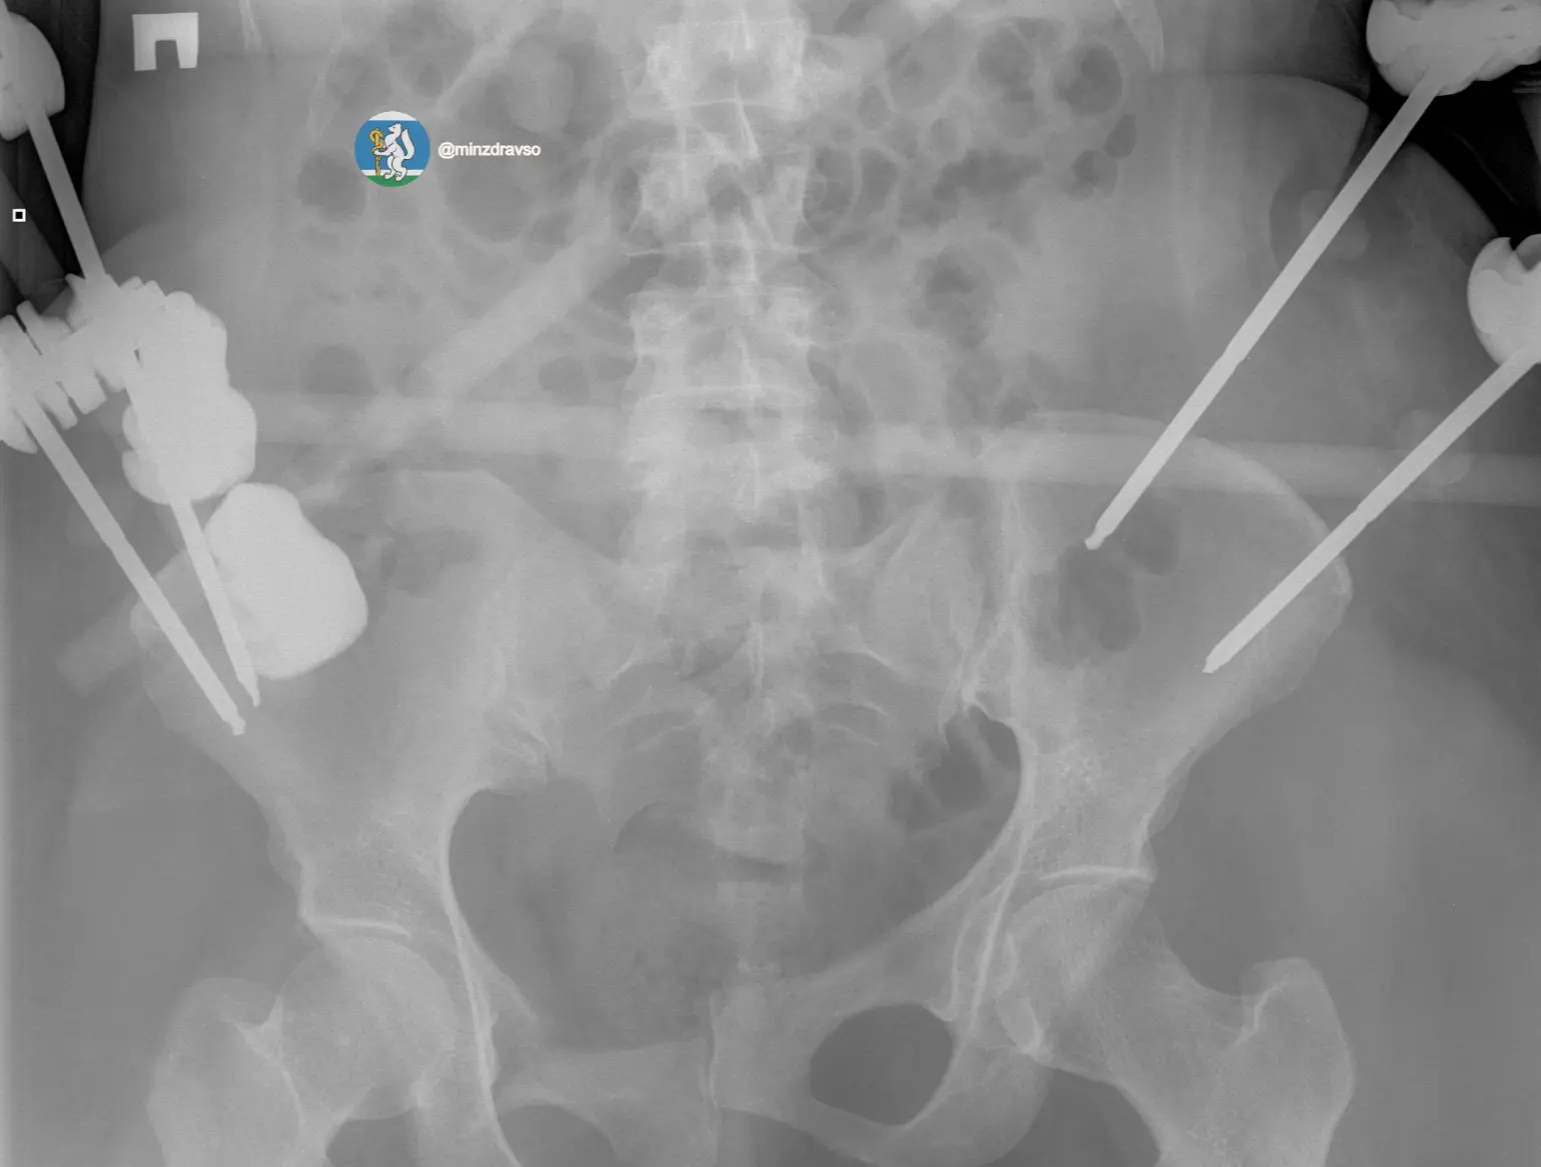

44-летнюю пострадавшую доставили в больницу в состоянии тяжёлого травматического шока — на грани жизни и смерти. Диагноз: закрытая черепно-мозговая травма, ушиб мозга, повреждение челюстно-лицевых костей, рёбер, двусторонний пневмоторакс, оскольчатый перелом ключицы и раздробленные кости таза.

Крайне тяжёлое повреждение таза грозило женщине массивной кровопотерей.

В первые 15 минут провели все необходимые исследования. Врачи скрепили отломки костей всех повреждённых сегментов аппаратами внешней фиксации, чтобы стабилизировать зоны переломов и купировать боль. Ключевую роль сыграл мультидисциплинарный подход: совместная работа анестезиологов-реаниматологов, травматологов-хирургов и нейрохирургов.

Тактика врачей позволила купировать шок и подготовить организм к основному хирургическому этапу. Затем аппараты внешней фиксации таза демонтировали и установили внутренние металлофиксаторы на ключицу и кости таза. Врачи не только спасли пациентку с тяжелейшими повреждениями, но и минимизировали последствия травм, сохранив качество жизни. Через месяц после аварии женщина вернулась домой.